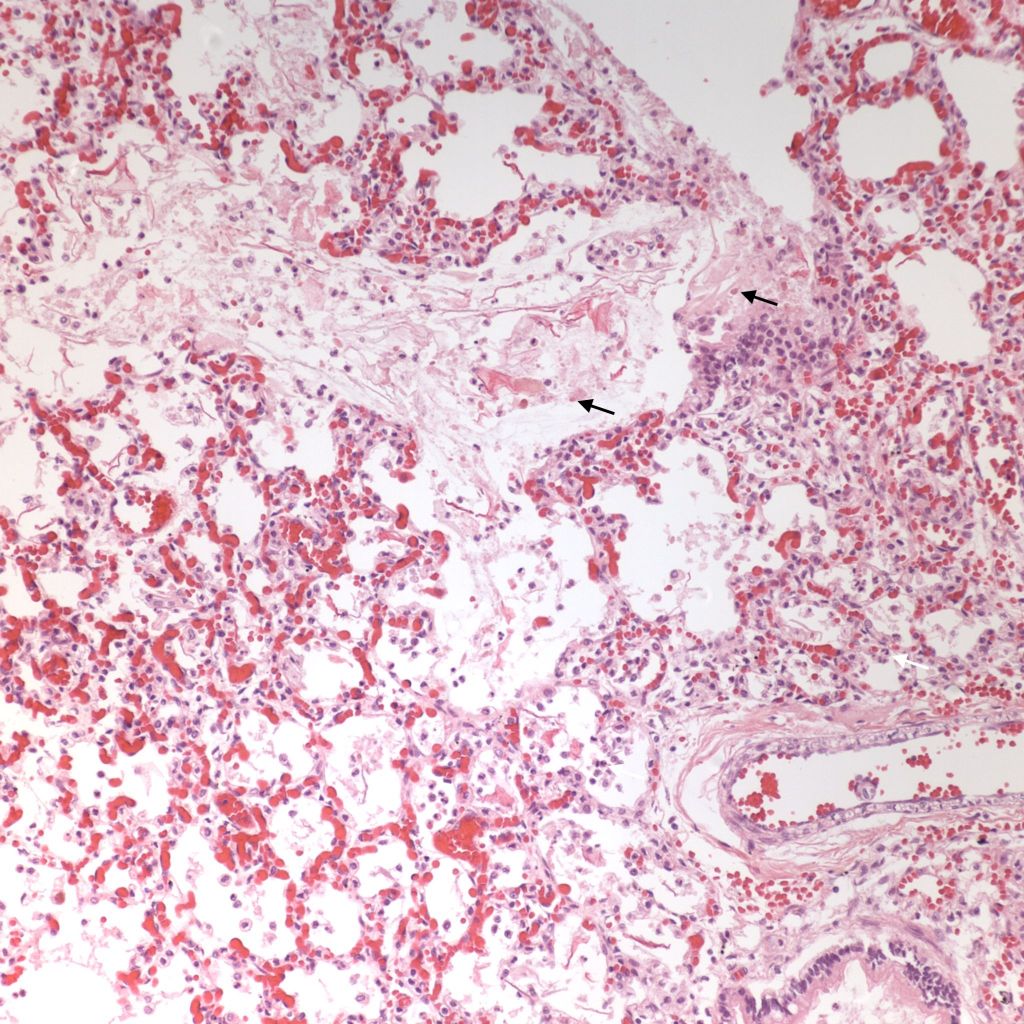

Beside hemorrhage in the visceral pleura, there may be deeper connective tissue interstitial hemorrhage in the lung. The capillaries in other areas of the lung with pleural petechiae are often engorged as well, and the rigors of gasping and pressure change may account for deeper hemorrhages (Fig 20a, b).